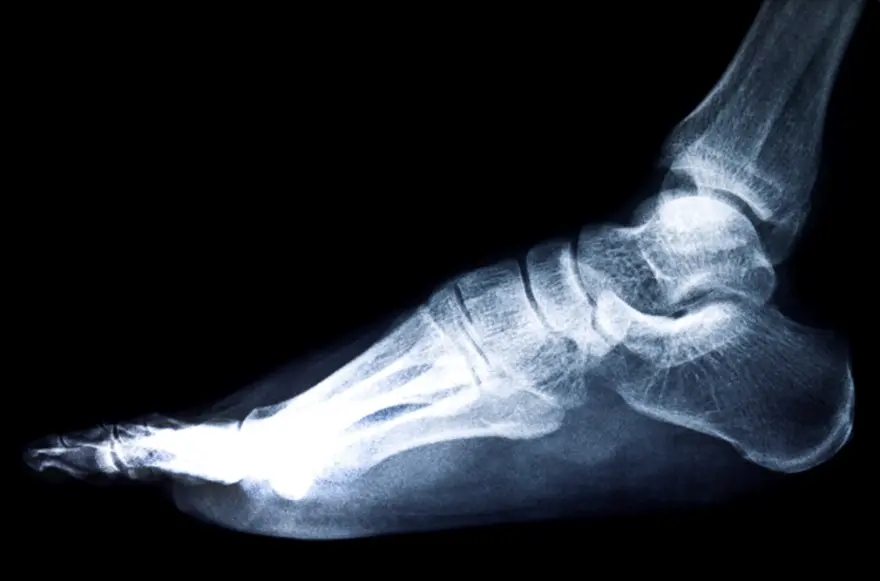

An osteophyte is a smooth, bony outgrowth that develops along the edges of bones, particularly where bones meet at joints or along your spine. These bone spurs form gradually as Your body’s adaptive response to mechanical stress, pressure, or cartilage damage. The development of bone spurs often accompanies conditions like osteoarthritis, where cartilage breakdown triggers your body's repair mechanisms. Osteophytes typically appear as small, pointed projections on X-rays, resembling small bony ridges or spikes extending from the bone’s surface.

Heel spurs (calcaneal osteophytes) represent a specific type of bony outgrowth that forms on the underside of the heel bone where the plantar fascia attaches. This bone spur often develops alongside plantar fasciitis, creating sharp, stabbing heel pain that's typically worst with your first steps in the morning or after prolonged sitting.

• X-rays are the primary imaging method for visualising bone spurs and assessing joint space narrowing